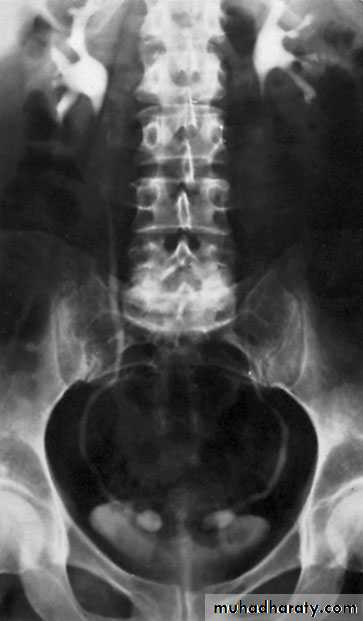

Ureteral duplication: partial and complete

Partial duplication: is more common. Two ureters draining single kidney for variable length, then unite together before entering the bladder in one ureteric orifice. Rarely the lower part is duplicated as inverted Y ureter.Complete duplication:

Less frequent, the whole ureter is duplicated, and each one opens in separate orifice in the bladder. The ureter draining the upper partopens more distally

in the bladder.

Bifid renal pelvis

iComplete ureteral duplication and ectopic ureteric orifice.